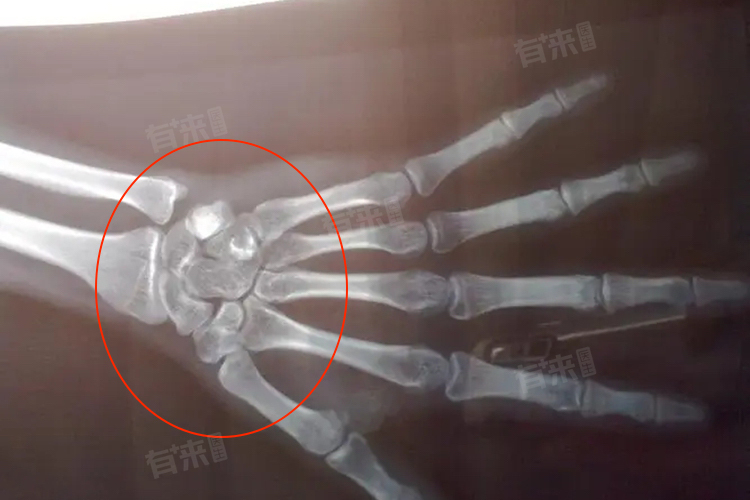

- 骨骼闭合即骨骺线闭合,是骨骼生长发育的一个重要标志,骨骺线是长骨两端软骨组织中的一层软骨,随着生长发育的进行,这层软骨会逐渐骨化,最终与骨干融合,形成一条紧密的骨线,即骨骺线闭合,一旦骨骺线闭合,骨骼的长度基本确定,身高增长的空间也随之减少。

- 通常情况下女孩的骨骼闭合年龄在15岁左右,但具体时间因人而异,受到遗传、营养、运动等多种因素的影响,因此15岁的女孩有可能已经出现骨骼闭合的情况。

- 如果15岁女孩的骨骼已经完全闭合,身高增长的空间通常非常有限,因为骨骼闭合意味着生长板已经完全融合,无法再通过生长板的活动来增加身高。